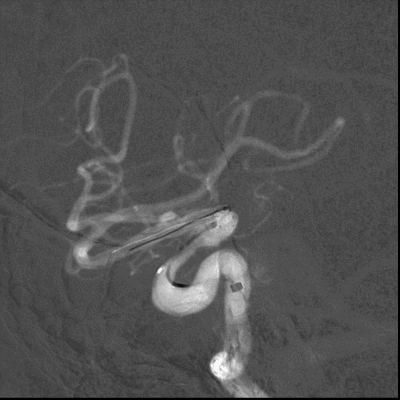

将6F 115cm SKATHI远端通路导管撤至左侧颈内动脉C1起始,多角度造影显示左侧颈内动脉眼动脉段狭窄明显改善,颈内动脉通畅,颅内血流改善。

患者术后病情平稳,无不适主诉。